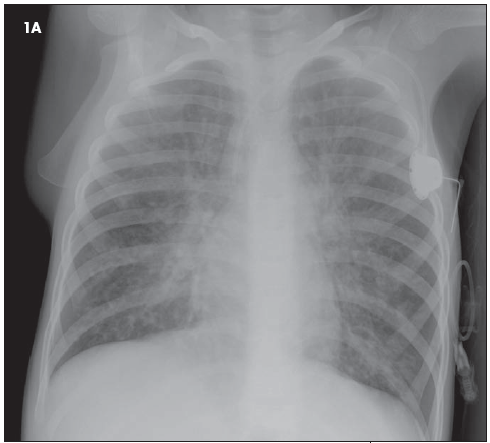

1. The chest radiographs (Figure 1) of a 9-year-old child reflect the classic findings of a particular disease. Among other findings, the size of the patient's heart is_____?

1. The chest radiographs (see Figure 1) of a 9-year-old child reflect the classic radiographic appearance of CF. Among other findings, the size of the patient's heart is small to normal. (B is the correct choice.)

The patient's heart is probably of normal size, but the hyperexpansion commonly seen in patients with CF may make it seem relatively small. This phenomenon is frequently observed in older patients with emphysematous lungs. A small cardiac silhouette may also be seen in patients with asthma. The finding of microcardia could also suggest a hypovolemic state in other patients.

Other common radiographic and cross-sectional imaging (CT) findings of CF include focal atelectasis with or without hyperaeration, bronchiectasis seen as dilated tubular tracts or end-on with a cystic appearance, parahilar streaky opacities, peribronchial thickening, and mucous plugging.

3. Is there evidence of hyperinflation? The answer is yes. (A is correct.)

If the frontal view isn't enough to persuade you (count the 10 to 11 posterior ribs on the frontal view), take a look at the lateral view. The diaphragms are nearly completely flattened and there is a barrel shape appearance to the chest that results from anterior expansion (the anterior clear space) and bowing.

The radiograph shown here (see Figure 1) was interpreted without the benefit of earlier films at our institution. Thus, the presence of acute findings cannot be determined. (C is the correct choice.) Although no acute findings are suspected, a more confident interpretation would be possible if earlier films had been submitted for comparison.